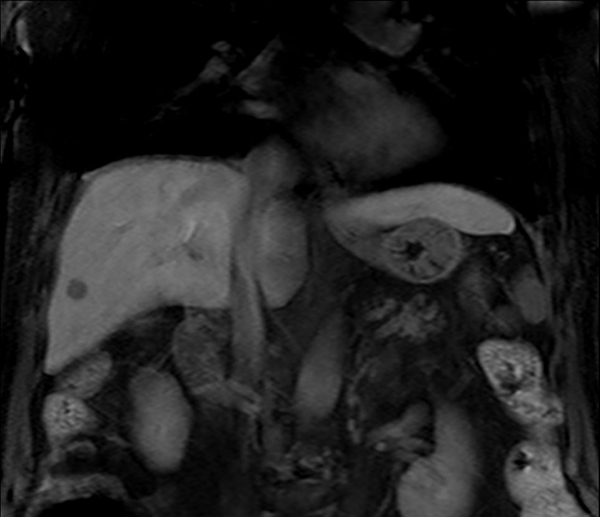

Coronal eTHRIVE